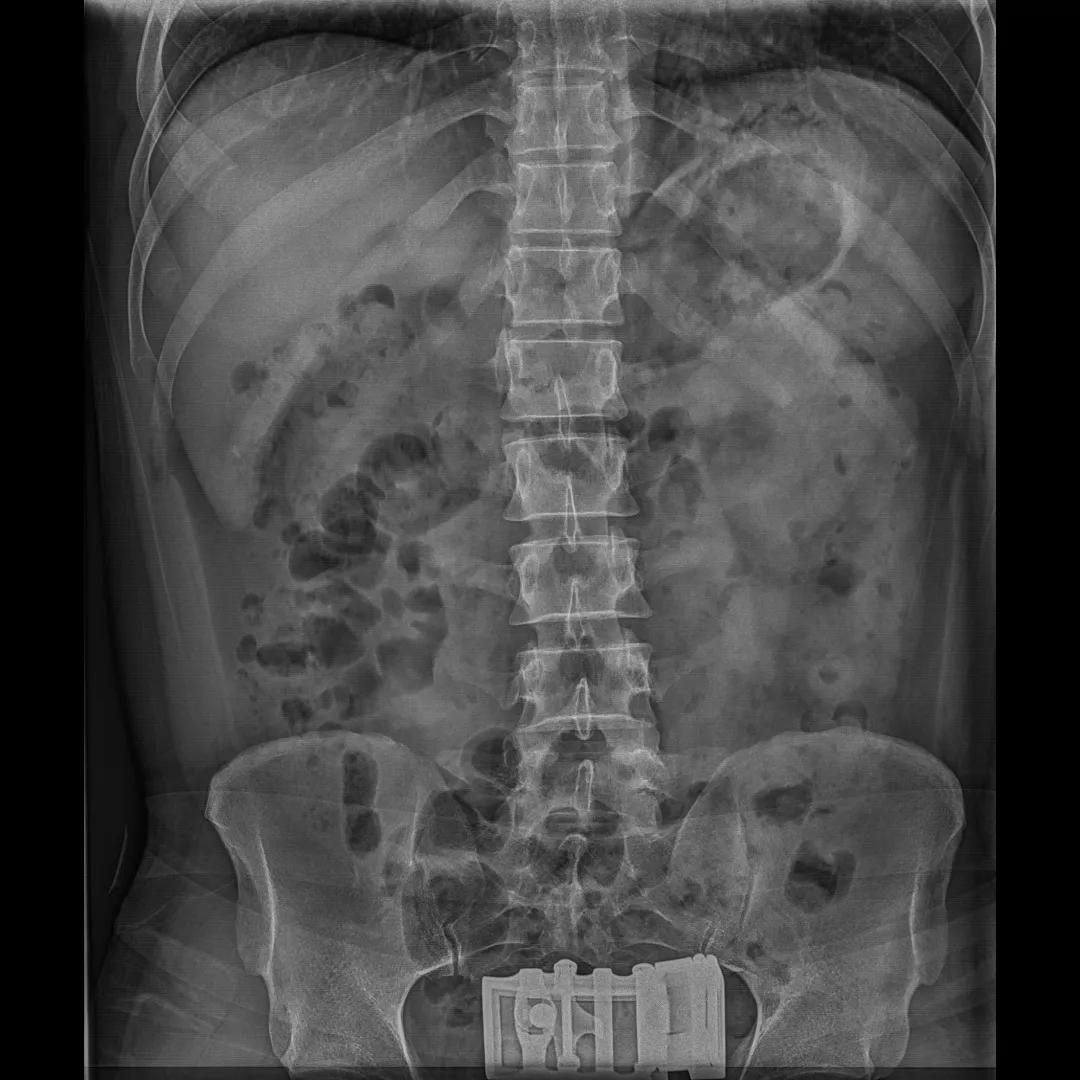

最后来看看“飞燕”的临床成像:

滑动查看更多图片